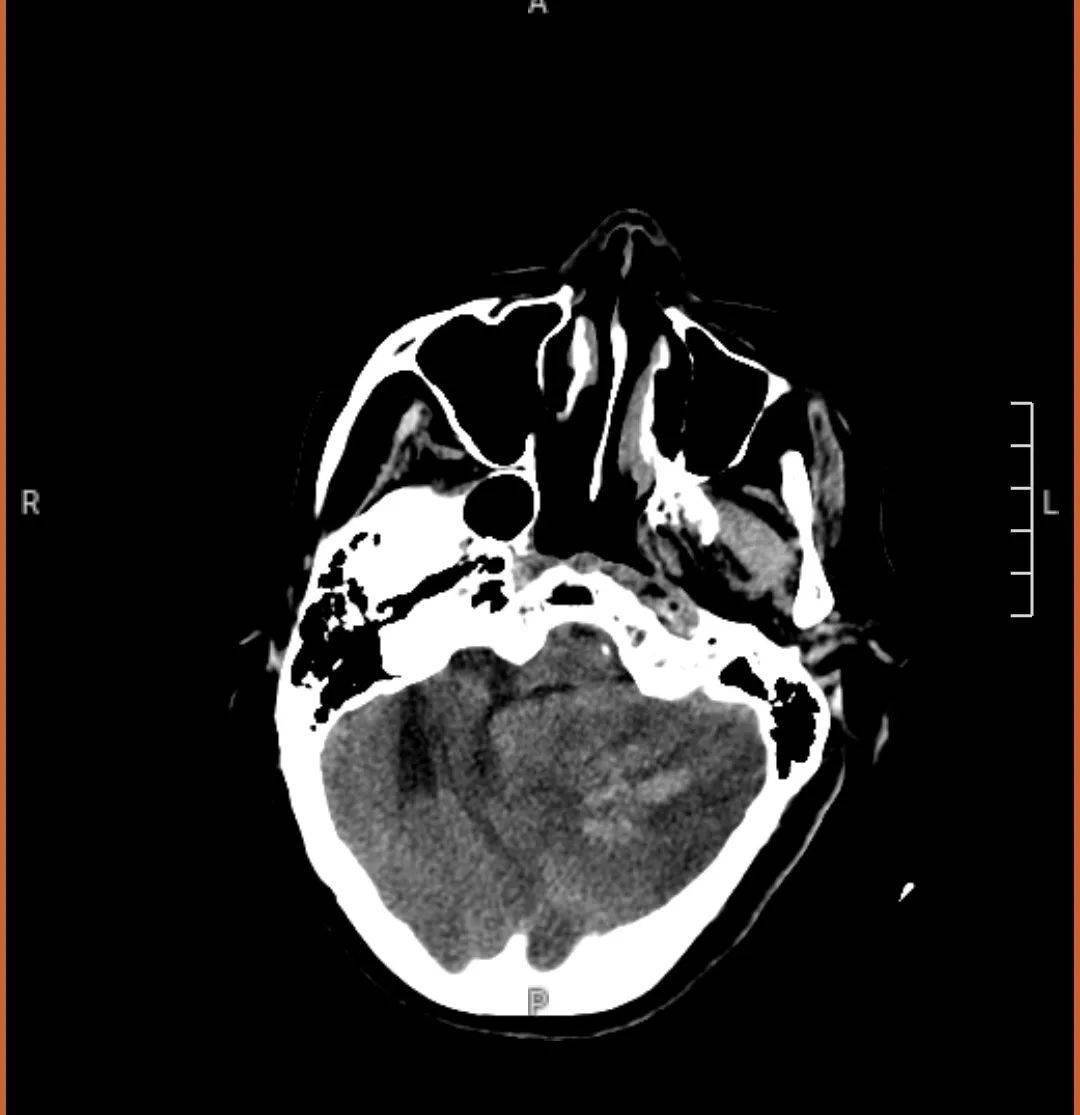

的河南省永城市某医院,查头颅ct未见明显异常(图-1);次日再查头颅核磁

颅脑核磁共振科室值班医生尹洪涛结合患者临床表现及大面积小脑梗死

头部核磁平扫可见左侧半球多发脑梗塞,这就是患者反复缺血发作导致的.

颅脑核磁示左侧丘脑新近梗死灶;多发腔隙性脑梗死,缺血灶;mra 未见